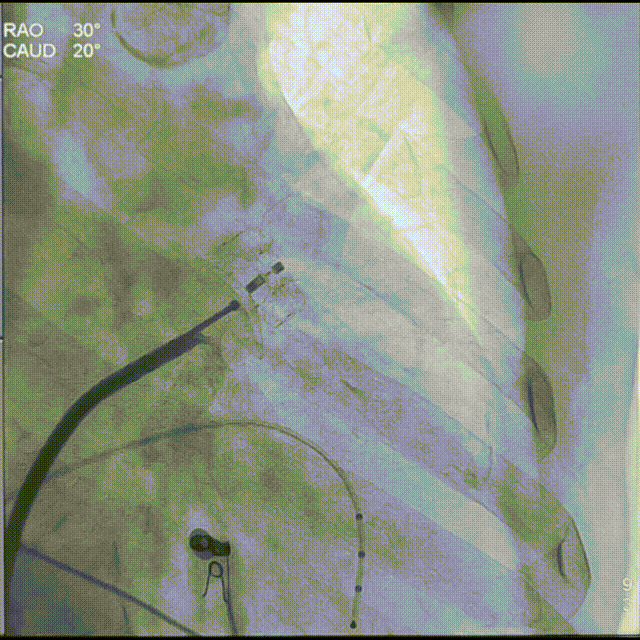

Laager®封堵器2429型号封堵盘展开后造影

随后,进行牵拉试验时发现封堵器可拉出心耳,未锚定成功。因此决定增大封堵器型号,换用Laager®封堵器2631型号;

Laager®封堵器2631型号封堵盘展开过程